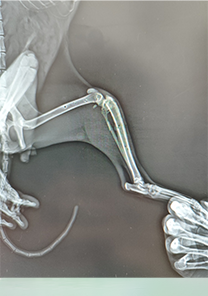

Muhammed Bey'in Kedisi

Muhammed Bey'in kedisi, beşinci kattan düşmeye bağlı olarak tibia ve fibulasında üç parça halinde kırık tespit edilmiştir. Plak uygulaması ile fiksasyonu yapılan kedinin, Operasyonun ardından bir hafta sonra yürüme ve ağrı semptomları tamamen kaybolmuştur. Operasyon günü itibarıyla MN - HUND&KATT kullanılmıştır.